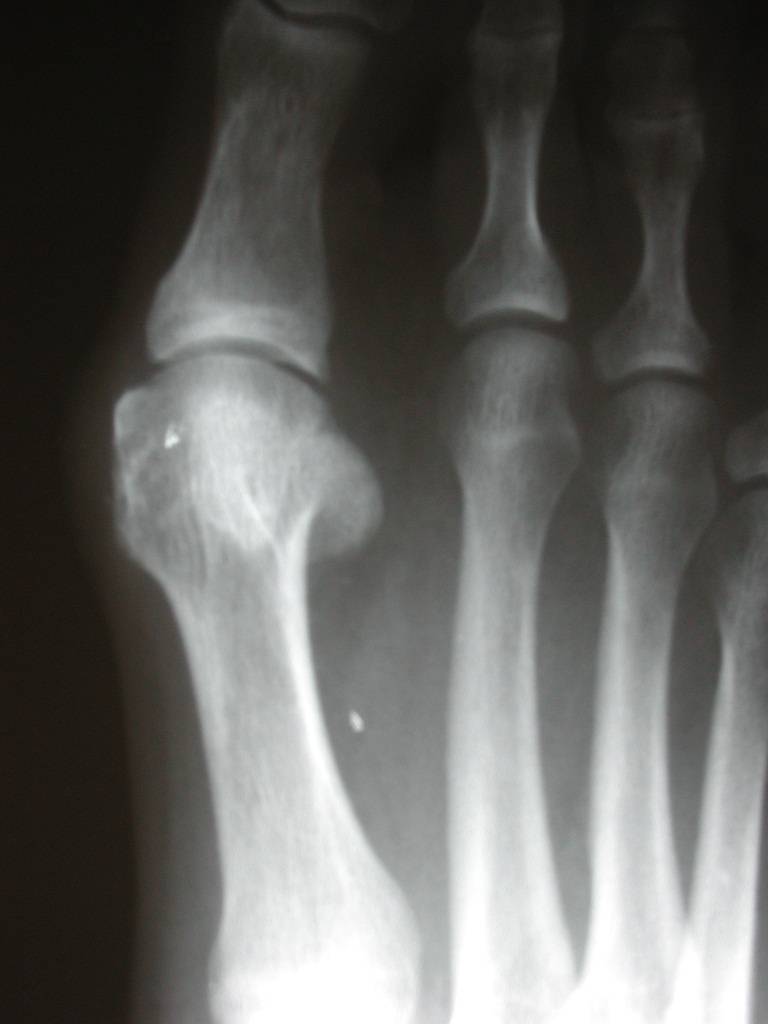

From www.learningradiology.com

LearningRadiology Tailor's, Bunion What Does A Bunion Look Like On X Ray Ultrasound is sensitive enough to detect urate crystals in an affected joint. They may be tender on palpation. Bunionettes are visible on clinical examination as an erythematous swelling overlying the 5 th metatarsal head. What Does A Bunion Look Like On X Ray.